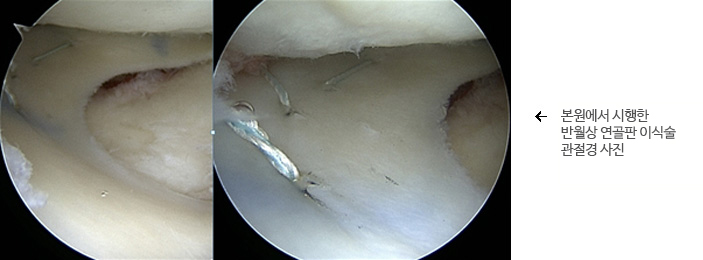

관절경을 이용하여 수술을 시행하게 됩니다. 약 5cm 정도의 추가 절개를 가하게 되고 이식할 연골을 삽입하게 됩니다. 이식되는 반월상 연골은 우선적으로 경골에 실을 이용해서 일차적으로 고정하게 되고 고정된 위치를 확인한 후에 여러 개의 실을 이용하여 확실하게 고정하게 됩니다.